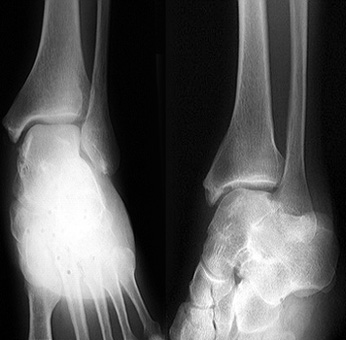

Look at the radiographs below. The talo-calcaneal coalition is best seen on the oblique view. Can you see it? Look for disruptions of the subtalar joint.

AP and oblique views